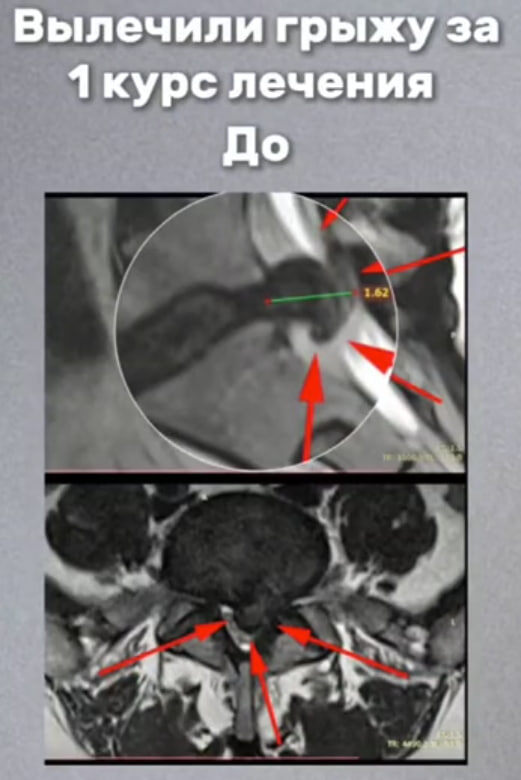

"ДО" грыжа L5-S1, сагиттальный размер 1,6 см, абсолютный стеноз канала